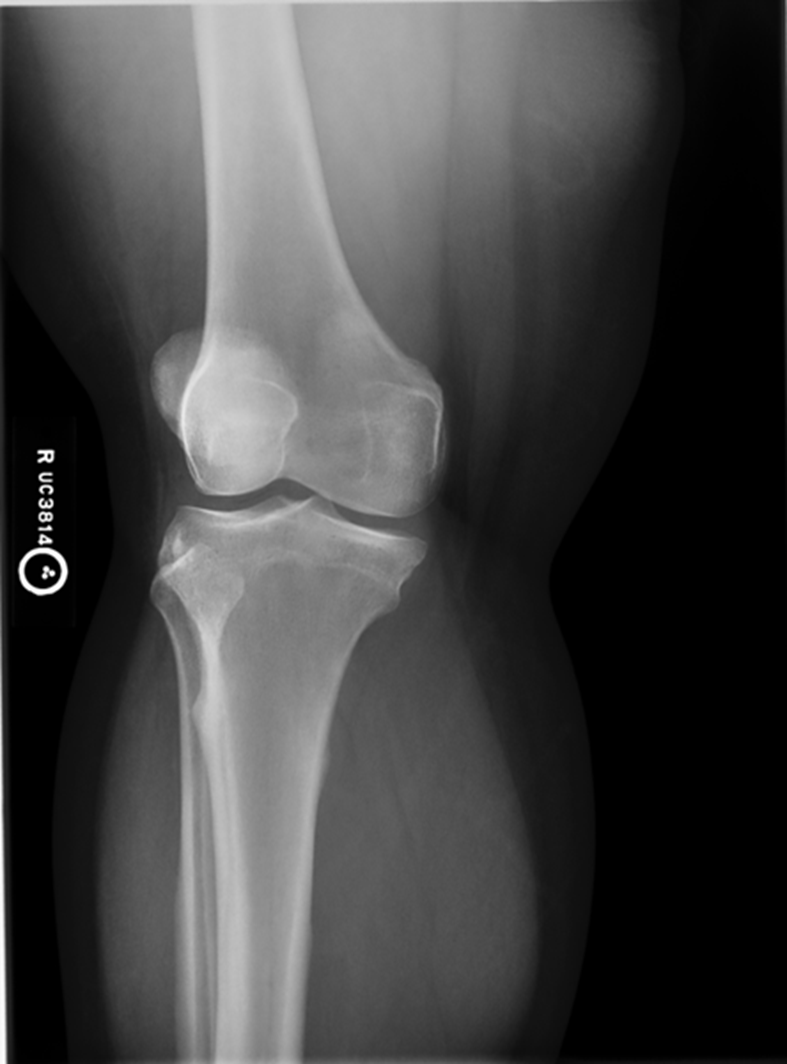

Patella is in the center! good! equal distance of joint space/platoes which is good

ACCEPTABLE BECAUSE EVERYTHING ELSE IS GOOD! PATIENT COULD HAVE A MORE SEPARATED FIBULAR HEAD! THEIR ANATOMY IS DIFFERENT. CENTERING IS GOOD